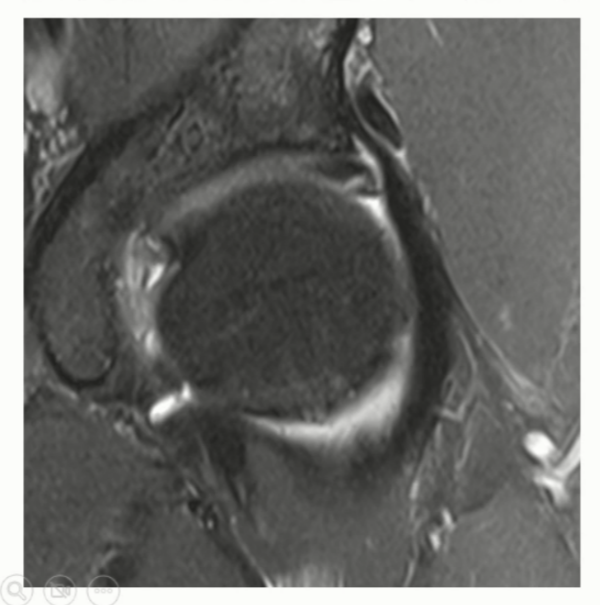

Case 2)

아래 사진은 labrum 자체에 degenration이 있는 경우